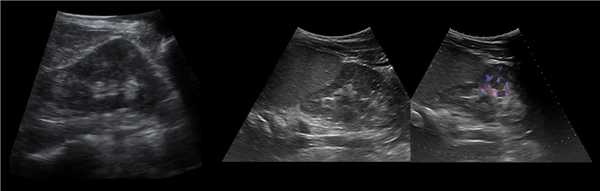

а) Эхограммы.

б) Серия компьютерных томограмм.

У 2 (1,2%) больных отмечена увеличенная "губа" над воротами почки (рис. 3а-в).

а) Эхограмма.

б) Экскреторная урограмма.

в) КТ с контрастным усилением.

Наиболее частой причиной псевдоопухоли была "гипертрофия" столбов Бертена или "перемычки" паренхимы почек - у 153 (86,4%) пациентов (рис. 3 г-е). "Перемычки" паренхимы были отмечены не только при различных удвоениях чашечно-лоханочных систем почек, но и при различных их сращениях и незавершенных поворотах почек.

Рис. 3 (г-е). Псевдоопухоль гипертрофия Бертена (неполная "перемычка" паренхимы) в среднем отделе правой почки.

г) Эхограмма.

д) Экскреторная урограмма.

е) КТ с контрастным усилением.